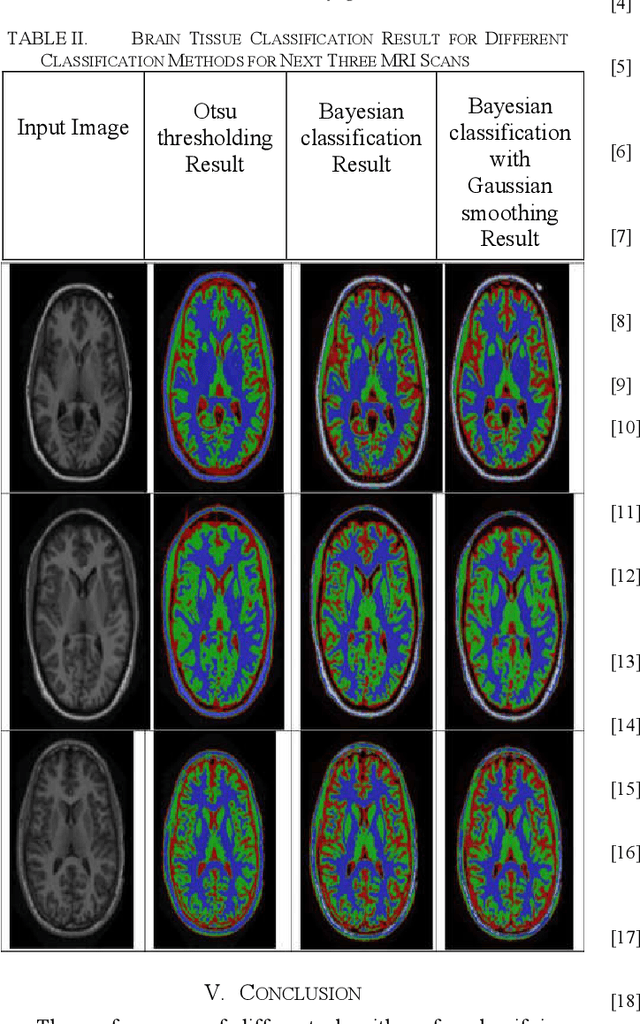

Abstract:Tissue classification is one of the significant tasks in the field of biomedical image analysis. Magnetic Resonance Imaging (MRI) is of great importance in tissue classification especially in the areas of brain tissue classification which is able to recognize anatomical areas of interest such as surgical planning, monitoring therapy, clinical drug trials, image registration, stereotactic neurosurgery, radiotherapy etc. The task of this paper is to implement different unsupervised classification algorithms in ITK and perform tissue classification (white matter, gray matter, cerebrospinal fluid (CSF) and background of the human brain). For this purpose, 5 grayscale head MRI scans are provided. In order of classifying brain tissues, three algorithms are used. These are: Otsu thresholding, Bayesian classification and Bayesian classification with Gaussian smoothing. The obtained classification results are analyzed in the results and discussion section.